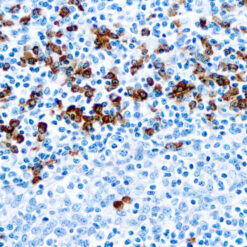

CD7 is expressed by most peripheral blood T cells, NK cells, and all thymocytes. It is one of the earliest surface antigens on T and NK-cell lineages. The antibody is a useful aid for classification of T-cell malignancies.

| Positive Control Tissue | Tonsil |